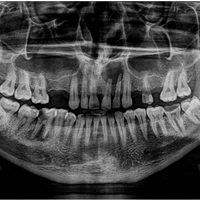

Pacjent z rozległa torbielą 21, 22. Po przygotowaniu endodontycznym wykonano zabieg resekcji. Na uwagę zasługuje delikatne wykonanie zabiegu - na błonie śluzowej i dziąsłach nie sa widoczne blizny pozabiegowe, co jest bardzo ważne u pacjenta z wysoka linią uśmiechu.